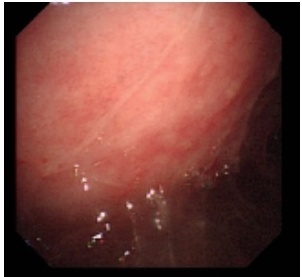

病史摘要:70 岁男性患者,因“反复肤黄尿黄 10 年余,咳嗽、胸闷 3 天”入院。既往有高血压、糖尿病史,2015 年服中成药后出现肤黄尿黄、肝功能异常,2024 年外院 MR 提示肝硬化,2025 年 4 月症状加重,多种指标异常,加用 UDCA 治疗;5 月我院诊断自身免疫性肝炎,予甲泼尼龙及吗替麦考酚酯治疗。此次入院前 3 天出现全身无力、头晕、咳嗽、胸闷。 诊疗过程:入院查体生命